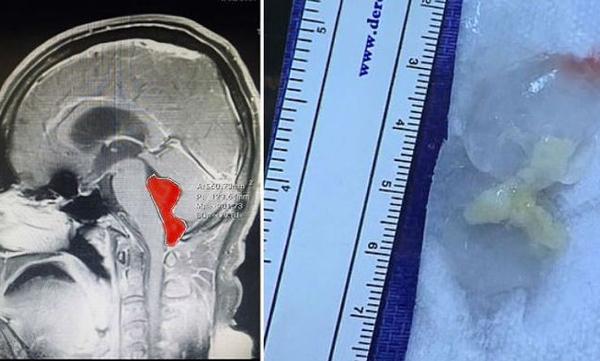

തലവേദന കാരണം ജോലി പോലും ചെയ്യാന് സാധിക്കാതെ വന്നതോടെയാണ് ഇദ്ദേഹം ആശുപത്രിയിലേക്ക് പോയത്. ആദ്യഘട്ടത്തില് മൈഗ്രെയ്ന് ആയിരിക്കാം എന്ന നിഗമനത്തിലായിരുന്നു ഡോക്ടര്മാരും. എന്നാല് വിശദപരിശോധനയില് സംഗതി മൈഗ്രേയ്ന് അല്ലെന്ന് കണ്ടെത്തി. പിന്നീട് തലച്ചോര് സ്കാന് ചെയ്തു നോക്കി. അപ്പോഴാണ് തലയ്ക്കകത്ത് എന്തോ വളര്ച്ചയുള്ളതായി ഡോക്ടര്മാര് ശ്രദ്ധിച്ചത്. ട്യൂമര് ആയിരിക്കുമെന്നാണ് 90 ശതമാനവും അവര് ഉറപ്പിച്ചത്. എന്നാല് ഡോക്ടര്മാരുടെ ആ നിഗമനവും തെറ്റിക്കുന്നതായിരുന്നു. ഒരു തരത്തിലുള്ള പരാദമായ, വിരയായിരുന്നു ജെറാര്ഡോയെ പ്രശ്നത്തിലാക്കിയിരുന്നത്.

ആവശ്യത്തിന് പാകം ചെയ്യാതെ കഴിച്ച മാംസത്തില് നിന്ന് എപ്പോഴോ ശരീരത്തിലെത്തിയ വിരയായിരുന്നു ഇത്. തീരെ ചെറുതായിരിക്കുമ്പോള് തലയിലെത്തിയതാകാം. പിന്നീട് വര്ഷങ്ങളുടെ സമയമെടുത്ത് ഇത് പതിയെ വളര്ന്നതാണെന്നാണ് ഡോക്ടര്മാര് പറയുന്നത്. സാധാരണഗതിയില് ശരീരത്തില് കയറിക്കൂടുന്ന വിരകള് ഇത്രയും വലിപ്പമാകാറില്ലെന്നും ജെറാര്ഡോയുടെ കേസ് ഒരപൂര്വ്വ സംഭവമാണെന്നും ഇവര് പറയുന്നു. തലച്ചോറില് വിര താമസമാക്കിയതോടെ രോഗി മരിക്കാനുള്ള സാധ്യത വളരെ കൂടുതലായിരുന്നുവെന്നും അദ്ദേഹം രക്ഷപ്പെട്ടത് അത്ഭുതമാണെന്നും ഡോക്ടര്മാര് പറയുന്നു.